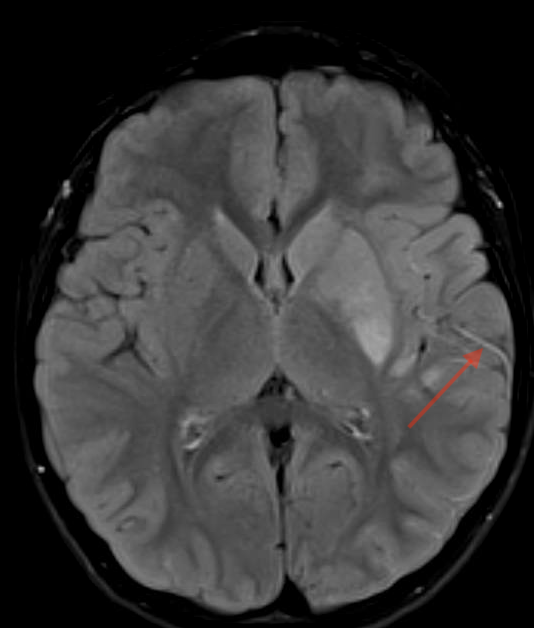

MR:

- flair hypersignaux vasculaires (ralentissement)

- dwi ↗ (œdème ctx)

- swi: signe du peigne (engorgement veineux médullaire ou perfusion de luxe)